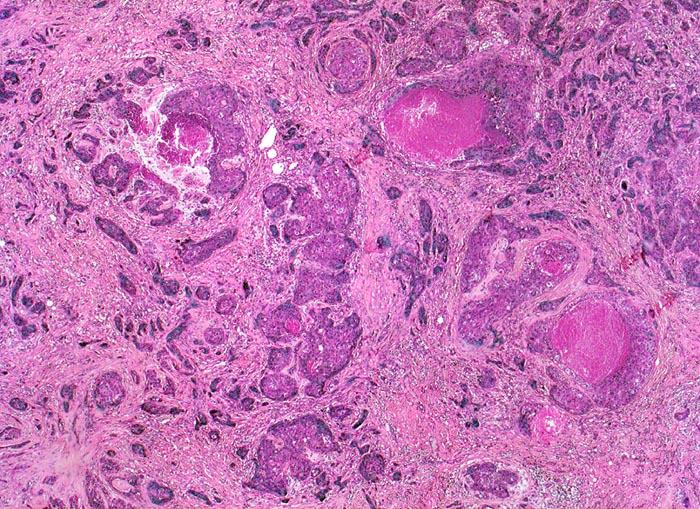

PathoPic – image database / PathoPic ID 4664 - wenig differenziertes invasives duktales Mammakarzinom

wenig differenziertes invasives duktales Mammakarzinom

Das Karzinom bildet keine drüsigen Strukturen, sondern ausschliesslich solide Zellstränge mit infiltrativem Wachstum in desmoplastischem Stroma. Fokal sind Tumornekrosen erkennbar.

Der vorliegende Tumor hat einen hohen Anteil solider Tumorareale, zeigt ausgeprägte Zellatypien und zahlreiche Mitosen entsprechend einem wenig differenzierten Karzinom.